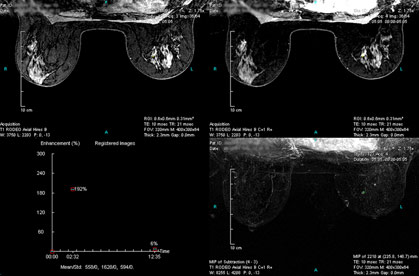

Case 1 - Left breast multi-focal cancers

(from left to right, top to down)

RODEO Pre (unspoiled), 1st Post (spoiled), MIP of Subtraction (1st Post – Pre) and TIC curve on the first lesion site.